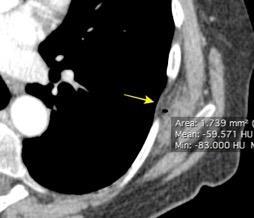

Densidad similar al músculo con estriaciones internas de grasa

Hallazgo incidental . Región infraescapular 2% de TC del tórax. Bilateral 60%.

Burt AM et al. Imaging review of lipomatous musculoskeletal lesions. SICOT J2017/ Murphey MD et al. From the archives of the AFIP: benign musculoskeletal lipomatous lesions. Radiographics. 2004